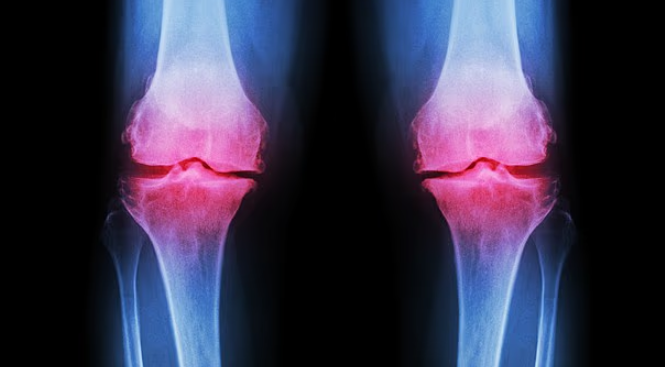

التهاب المفاصل العظمي يظهر مبكراً بين الأجيال الجديدة

أظهرت بيانات طبية أن التهاب المفاصل العظمي، الذي يصيب نحو 10 ملايين شخص في المملكة المتحدة، لم يعد مقتصراً على من تجاوزوا منتصف العمر. وأوضح الخبراء أن الحالة تنشأ عندما يتآكل الغضروف الذي يعمل كممتص للصدمات بين العظام، ما يؤدي إلى احتكاك مؤلم وتيبس وتورم. وأشاروا إلى أن الإصابات الرياضية المتكررة قد تغيّر ميكانيكا المفصل وتُسرّع هذا التدهور.